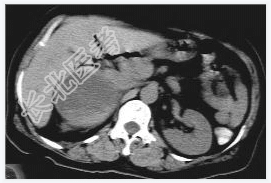

- [材料题] 女性,59岁,胸闷、头晕2天,呈持续性,伴呕吐,以进食后明显。发现“高血压”10年,“糖尿病”2年。体格检查:血压70~210/30~120mmHg。

- 简答题1、该病患诊断是什么?

- 简答题2、鉴别诊断有哪些?

- 简答题3、右肾上腺嗜铬细胞瘤囊变的定义是什么?

- 简答题4、右肾上腺嗜铬细胞瘤囊变的临床意义是什么?

- 简答题5、右肾上腺嗜铬细胞瘤囊变的诊断和治疗上需要注意哪些事项?